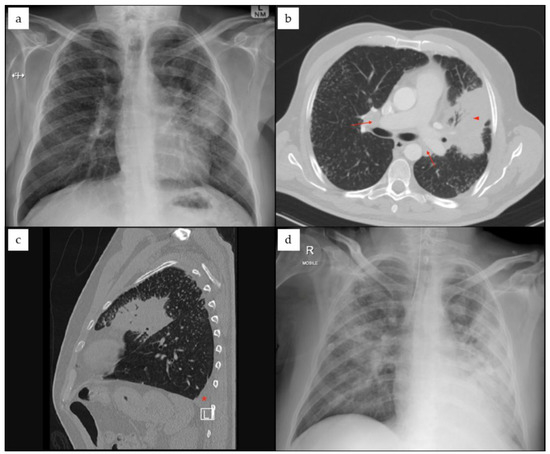

Background and Clinical Significance: Cladosporium cladosporioides is a ubiquitous dematiaceous mold that is rarely implicated in invasive human diseases and often considered a saprophyte and plant pathogen. Case Presentation: We report an extremely rare case of C. cladosporioides fungemia in a [...] Read more.

Background and Clinical Significance: Cladosporium cladosporioides is a ubiquitous dematiaceous mold that is rarely implicated in invasive human diseases and often considered a saprophyte and plant pathogen. Case Presentation: We report an extremely rare case of C. cladosporioides fungemia in a 61-year-old man with mantle cell lymphoma undergoing chemotherapy. The patient developed fever, dry cough and cavitary pulmonary lesions in the setting of profound immunosuppression. Blood cultures yielded slow-growing dark pigmented mold after prolonged incubation and species identification was achieved using MALDI-TOF mass spectrometry with an alternative fungal database, supported by microscopic morphology. Serum 1,3-β-D-glucan levels were markedly elevated, while galactomannan antigen testing was negative. Antifungal susceptibility testing demonstrated activity of triazoles and targeted therapy with voriconazole led to clinical improvement. A review of the literature identified only five previously reported cases of invasive C. cladosporioides infections worldwide, involving primarily pulmonary and central nervous system disease. Conclusions: To the best of our knowledge, this is the first documented case of fungemia caused by this species. The current report highlights the pathogenic potential of C. cladosporioides in immunocompromised hosts, the diagnostic challenges posed by slow-growing dematiaceous fungi, the importance of prolonged culture incubation, fungal biomarkers and advanced identification techniques for timely diagnosis and management. Full article